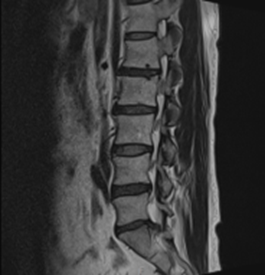

그림3.png 촬영 일시: 2025.03.25

<Fig 1. 요추 MRI>

요추 4-5번, 5번-천추1번 사이의 디스크 탈출

그것도 중심부와 왼쪽 신경을 누르고 있는 상황이었어요.

근전도 검사까지 해보니

요추 신경병증까지 확인됐고요.